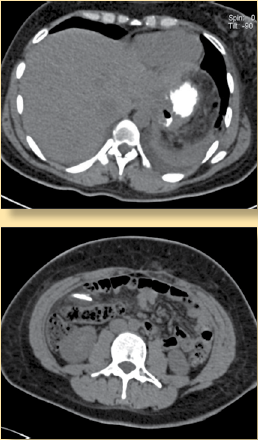

Se le realiza TC de control, en la que se observa que la banda gástrica ya no se encuentra rodeando al estómago (figura 2a y 2b); sin embargo, se identifica una imagen lineal de densidad metálica en el flanco derecho del abdomen en relación con un segmento de la banda migrada hacia el peritoneo; esto produce un efecto de cuerpo extraño con proceso inflamatorio agudo en este sitio (figura 3), por lo que en este caso se reporta como una complicación de la colocación y retiro de la banda gástrica.

Figura 2 Reconstrucción coronal de tomografía computada en donde se observa claramente el segmento de banda gastrica migrada hacia el peritoneo en el lado derecho del abdomen.

Figura 3 Estudio de tomografía computada (TC) postoperatoria de retiro de banda gástrica. a) Corte axial de TC con contraste oral en donde se observa que ya no existe banda gástrica en la topografía del estómago, pero no hay datos de perforación, extravasación de contraste ni líquido libre alrededor. b) Corte axial de TC a nivel de las siluetas renales, en donde se ve una imagen lineal de densidad metálica con importante proceso inflamatorio agregado alrededor en relación al segmento de banda gástrica migrada hacia el peritoneo en el lado derecho del abdomen.